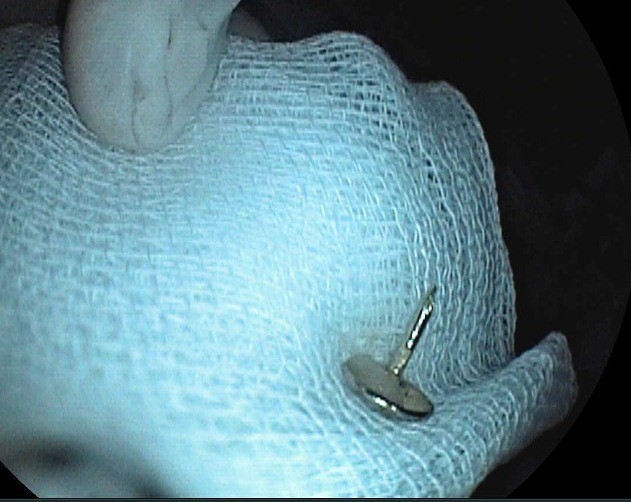

Chiếc đinh vít được lấy ra

Các bác sĩ đã tiến hành gây mê và nội soi can thiệp bằng ống mềm gắp dị vật thành công cho bé.

Bác sĩ Lại Thị Thu Trang, Phụ trách nội soi, Khoa Nội cho biết: Do thực quản của bệnh nhi rất nhỏ, nên các thao tác thực hiện gặp nhiều khó khăn. Với tính chất sắc nhọn của đầu đinh vít, nếu không loại bỏ kịp thời có thể gây tổn thương đâm thủng thành ruột, thậm chí có thể gây thủng nhiều vị trí mà chiếc đinh đi qua.